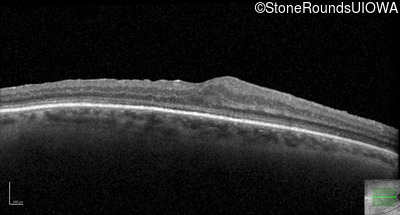

Optical Coherence Tomography - Left - 10/160 -1 sc

Exemplar / OCT Stack

OCT Stack